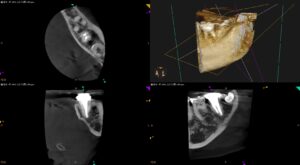

なぜ私の歯は痛むのか?根尖病変がないのに激痛があり,3件の歯科医院をたらい回しにされた患者さん〜#18 Re-RCTから7年経過

以前の記事の続報。 なぜ私の歯は痛むのか?根尖病変がないのに激痛があり,3件の歯科医院をたらい回しにされた患者さん〜#18 Re-RCTから5年経過 この時からさらに2年が経過した。 初診から振り返ろう。 主訴(2017 … 続きを読む なぜ私の歯は痛むのか?根尖病変がないのに激痛があり,3件の歯科医院をたらい回しにされた患者さん〜#18 Re-RCTから7年経過